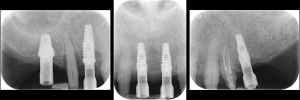

Periapical radiographs to verify the seat of the digital scan bodies. Fig. 12

Periapical radiographs to verify the seat of the implant- retained provisional restorations. Fig. 18